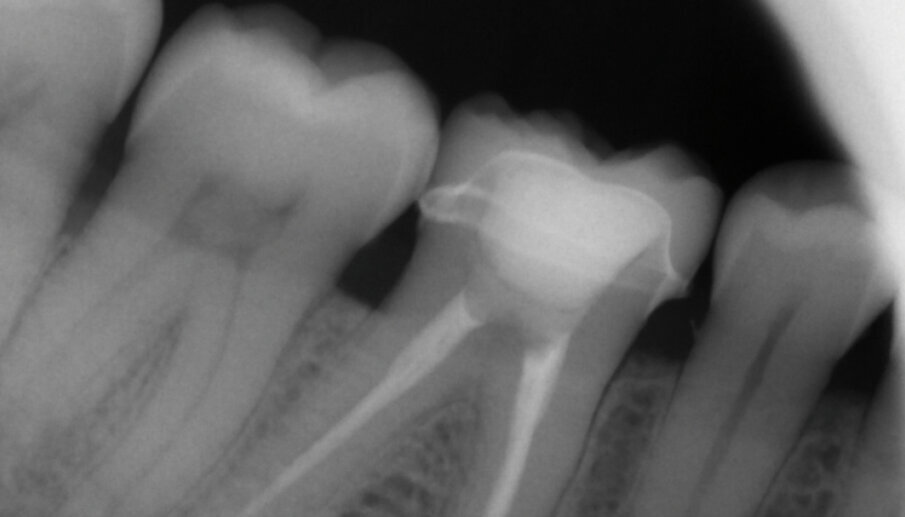

Fig. 13a: X-ray control image before and after the treatment

Fig. 13b: X-ray control image before and after the treatment

The adhesive (Tetric N-Bond Universal) was applied and dispersed with a strong stream of air. The dual-curing (DC) version of the Variolink Esthetic luting composite was used for seating due to the thickness of the crown and the low translucency of the ceramic material (Fig. 7). The luting composite was applied into the crown. Then the restoration was seated (Fig. 8) and light cured from each side for two seconds. Excess composite was easy to remove due to the Ivocerin photoinitiator, which provides a fast and thorough cure with a minimum amount of energy (Fig. 9). For final polymerization, the restoration was light-cured from each quarter for 20 seconds (Fig. 10). Figure 11 shows the oral situation after placement of the crown. Although the cement line is located above the gingival margin, it is not visible due to the favourable tone and opacity of the luting composite. Fig. 12 shows an X-ray control image of the restoration: the radiopaque build-up material and cement can be easily told from the tooth structure. This aspect is particularly important in situation where excess cement cannot be seen with the naked eye.